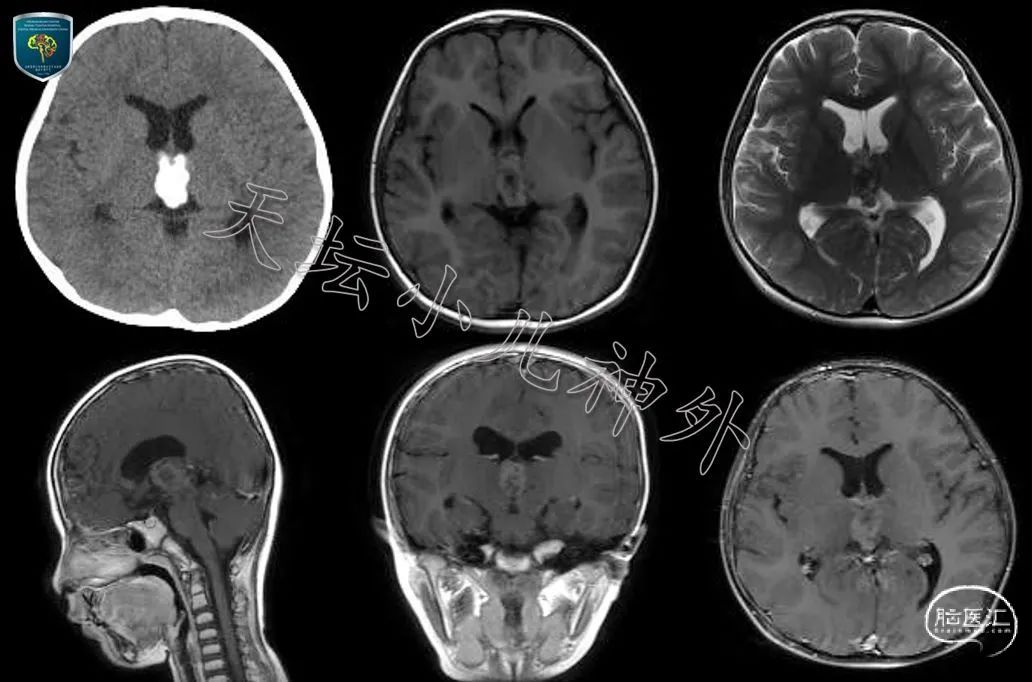

图1 四年前首诊时,头颅CT显示三室内钙化;头颅MRI显示三室内占位,轻微强化,畸胎瘤可能性大;鉴于无症状,未进一步诊治。